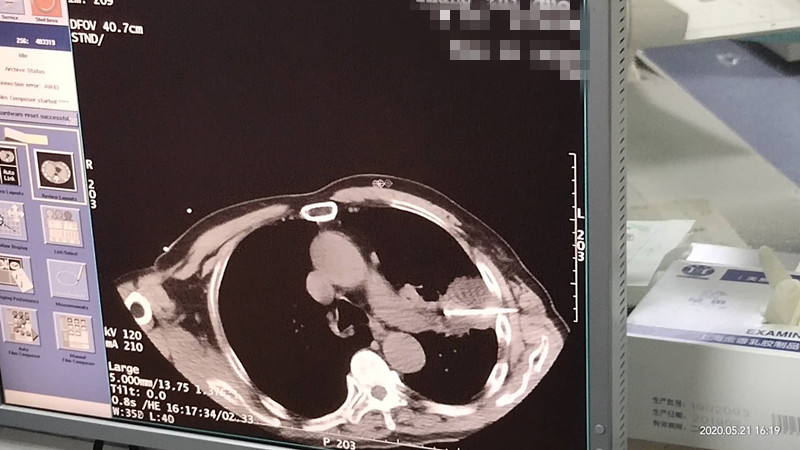

76岁肺部氩氦刀冷冻消融